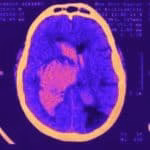

- Hematoma cerebral

- Hemorragia subaracnóide

- AVC maligno

- Drenagem de hematoma

- Craniectomia descompressiva